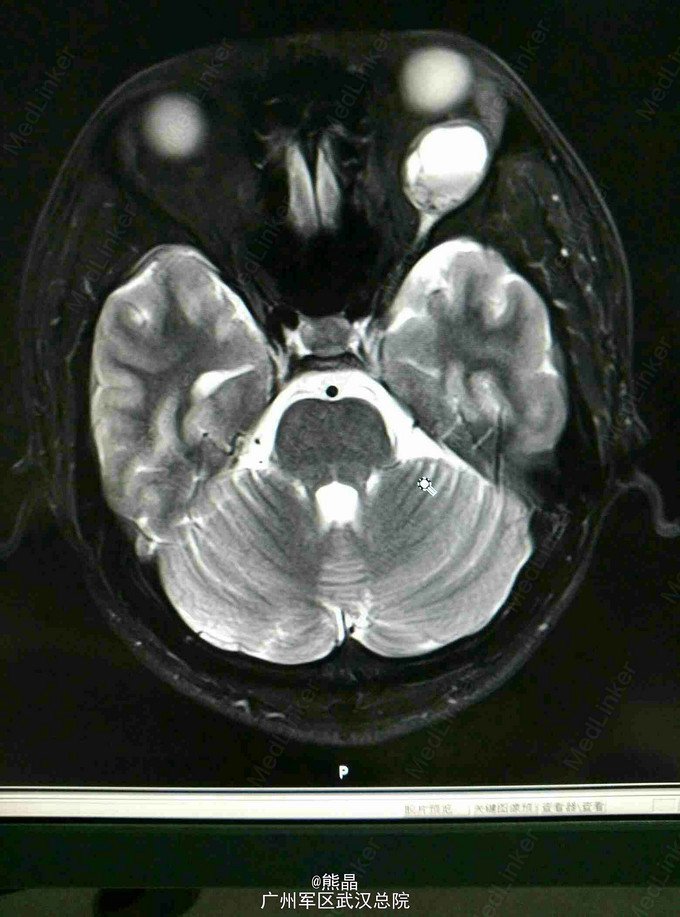

左眼眶神经鞘瘤的MRI表现一例

男性患者,27岁,左眼球突出2月余

MRI表现:左眼眶内球后肌锥内可见一椭圆形等T1长T2信号,内可见液平,增强呈斑片状强化,余未见明显异常

本院手术,术后病理,神经鞘瘤